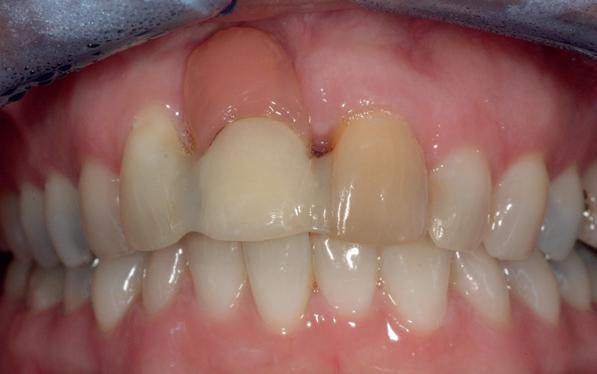

Een 47-jarige collega presenteert zich in onze verwijspraktijk voor endodontie. Hij heeft enige tijd geleden zijn kroon op de 11 laten vervangen (afbeelding 1). Omdat er geen klinische en röntgenologische aanwijzingen waren voor een periapicale laesie of een insufficiënte wortelkanaalbehandeling van de 11, werd besloten de endo, die dateerde van meer dan 30 jaar geleden, niet te reviseren (afbeelding 2). Tijdens een routinematige gebitsreiniging constateert zijn mondhygiënist een pocket van 7 mm aan de mesiopalatinale zijde van 11 (afbeelding 3). De nieuwe kroon wordt tijdelijk gecementeerd, en omdat

1: Klinische foto van bovenfront

3: Pocket palatinaal 11